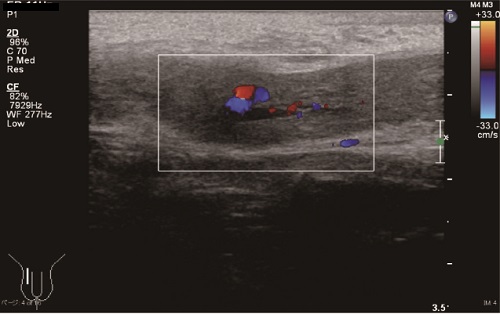

A 7-year-old boy was referred to our center with abnormal penile erection persisting for two days. He complained of mild pain without voiding symptoms. He had no history of trauma. Physical examination showed that the proximal two-third of the penis was tumescent with slight tenderness. Blood tests revealed no evidence of sickle cell anemia or other hematological diseases. Color Doppler ultrasonography (CDUS) showed increased inflow from the cavernous artery toward the corpus cavernosum on the right side. He was diagnosed as a case of non-ischemic priapism of unknown etiology. Spontaneous detumescence was noted after four weeks. At follow-up evaluation 16 months after diagnosis, he had not developed a recurrence. Follow-up CDUS revealed only a small arterio-cavernous fistula at the base of the right corpus cavernosum (Fig.1).